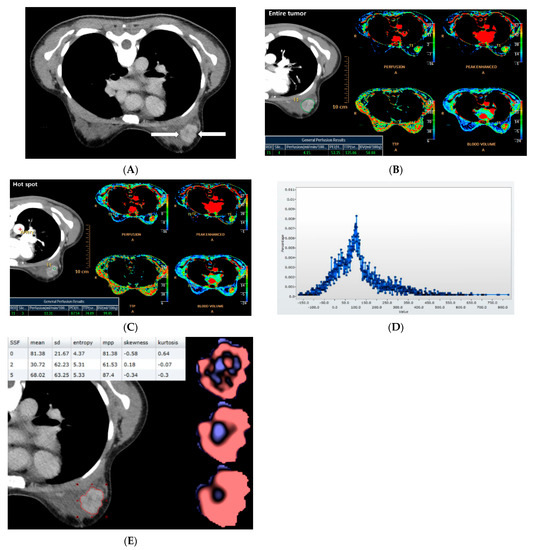

2.2. CT Acquisition and Analysis